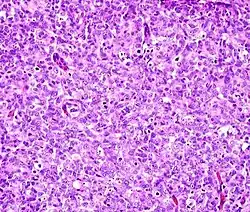

Histopathology

Micrograph showing contraction band necrosis, a histopathologic finding of myocardial infarction (heart attack).